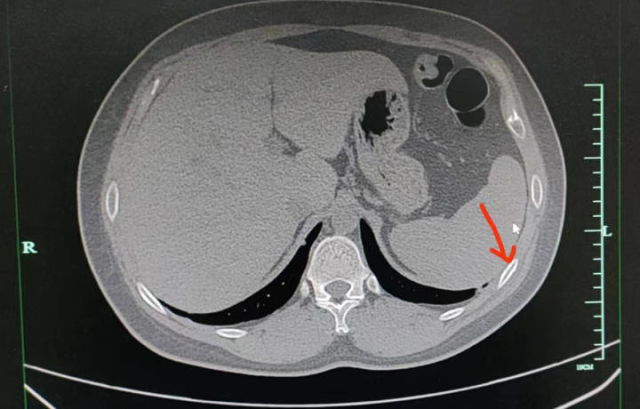

醫(yī)生注意到,正常狀態(tài)下,聶先生胸口只有輕微痛感,但在咳嗽或按壓時,疼痛會明顯加重。經過進一步的CT檢查證實,聶先生右側第五、第六肋骨都骨折了。

醫(yī)生解釋,肋骨骨折與其他骨折不同,它不承受重量,所以在靜息狀態(tài)下通常沒有疼痛感。但當肋骨受到外力按壓或胸廓活動較大時,如咳嗽或深呼吸,就會引發(fā)疼痛。

“咳斷肋骨的情況在骨質疏松的老年患者中較為常見。像聶先生這樣年輕、體型正常、營養(yǎng)均衡的患者是較少見的案例,可能是由于咳嗽時間持續(xù)過久,造成了肋骨部位反復受到牽拉而引發(fā)的疲勞骨折。”醫(yī)生表示。